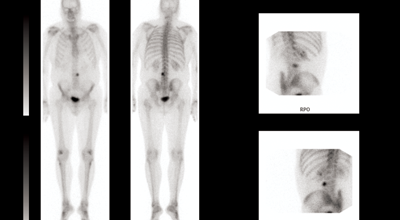

A 66-year-old man presented with a locally advanced T3b N1 prostate cancer in 2011, with an initial PSA of 33. He was treated with robotic prostatectomy and lymph node dissection followed by adjuvant prostate bed radiotherapy. Although immediate post treatment PSA levels were undetectable he had a PSA relapse in September 2012 to 2.1. Whole body MRI and Choline PET showed an apparent isolated left iliac lymph node recurrence (Figure 4). He went on to receive stereotactic radiotherapy (33Gy in 3 fractions to the lymph node - Figure 5). Follow-up imaging has shown a complete radiological response within the treated node. Eighteen months after treatment his PSA has started to rise again and most recent imaging has shown the development of a lymph node on the opposite side of the pelvis with no other sites of disease. He subsequently had further stereotactic radiotherapy to the right pelvic side wall nodes in July 2014. His PSA has dropped to 0.02 on his most recent check in January 2015.

Figure 4: Isolated pelvic lymph node recurrence on whole body MRI and Choline Pet and response to treatment.